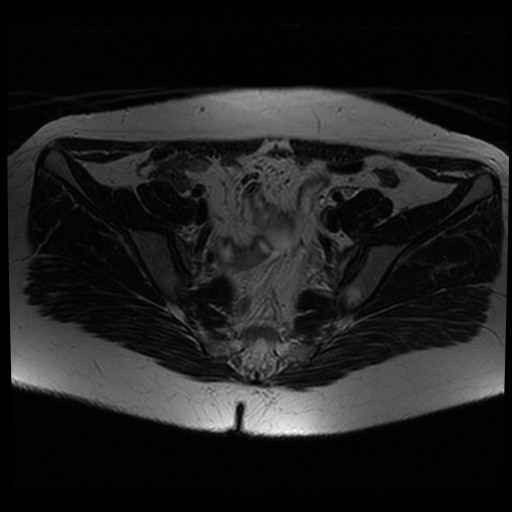

Bekken